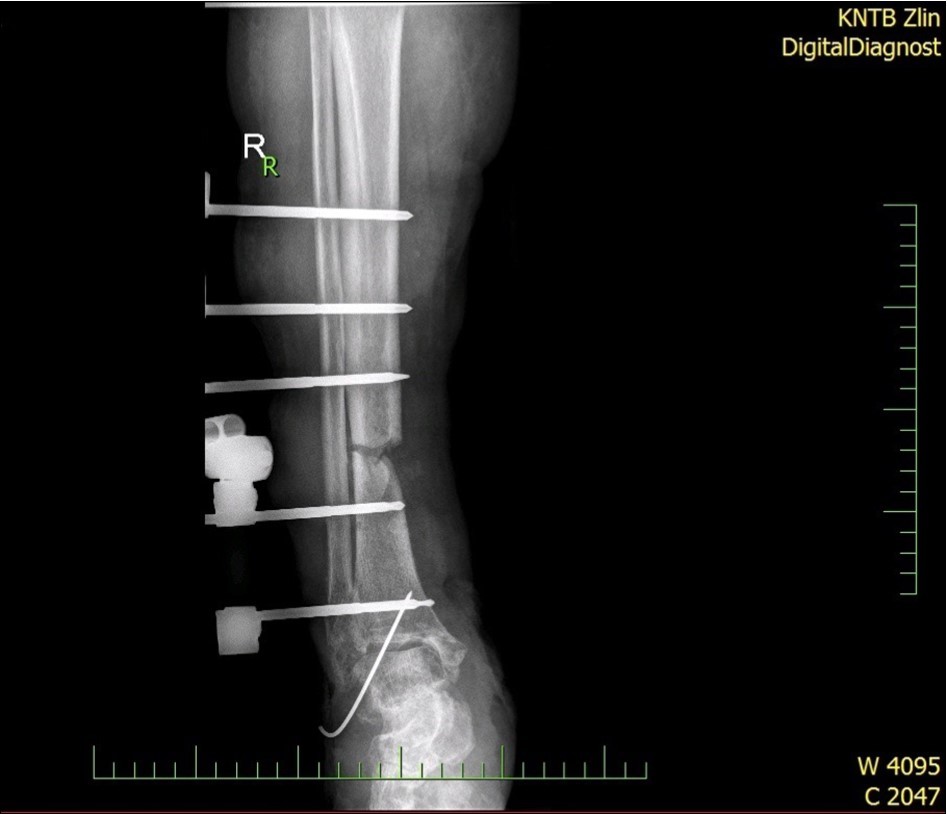

Figure 28.23 April. Surgery conversion of osteosynthesis. Removal external fixator and implantation intramedullary tibial nail. Gradual bone healing - last X-ray september 2019

Figure 29.23 April. Surgery conversion of osteosynthesis. Removal external fixator and implantation intramedullary tibial nail. Gradual bone healing - last X-ray september 2019